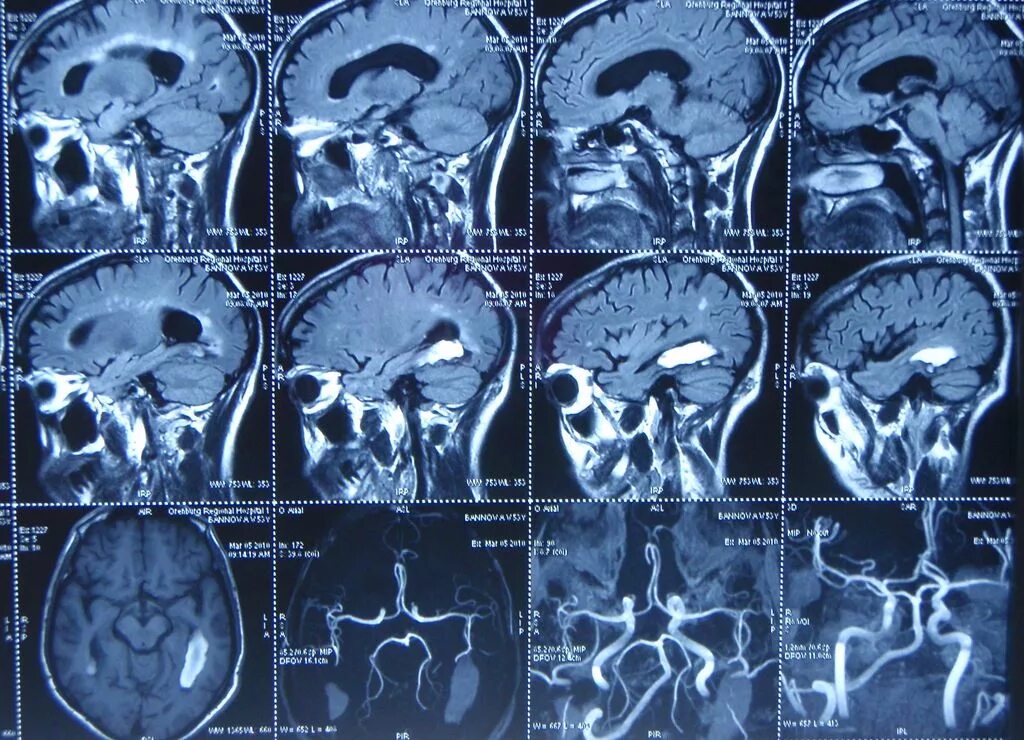

Можно ли с помощью мрт